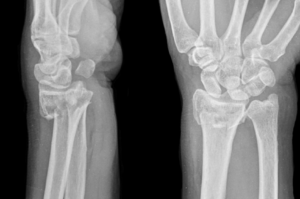

A distal radius fracture—commonly known as a broken wrist—is one of the most frequent orthopedic injuries seen in adults. This type of fracture occurs when one of the two bones in the forearm, the radius, breaks near the wrist joint. It often happens after a fall on an outstretched hand orfrom a high-energy injury like a car accident, sports trauma, or work-related accident.

The radius bone runs along the thumb side of your forearm and connects with the carpal bones at the wrist joint. When this bone breaks close to the wrist, it is referred to as a distal radius fracture. Depending on how the wrist bent backward during injury, patients may sustain a Colles

fracture (radius tilts upward) or a Smith fracture (radius tilts downward). A Colles fracture occurs when the wrist is bent backward after falling on an outstretched hand, which is one of the most common injury mechanisms.

Many wrist fractures occur when someone falls onto an outstretched hand or lands on a bent wrist. While some breaks are clean and stable, others are displaced, comminuted, or intra-articular fractures that extend into the joint surface. These fractures may involve the radial styloid, the small bony prominence on the outer edge of the wrist, or extend into nearby carpal bones like the scaphoid. It’s not unusual for distal radius and scaphoidfractures to occur together in severe trauma.

A proper diagnosis begins with a physical exam and review of your injury history.

Dr. Chambers will assess the soft tissues, ligament injuries, and nerve function, followed by X-rays of the wrist.

In complex or intra-articular fractures, advanced imaging such as CT scan or magnetic resonance imaging (MRI) may be ordered to evaluate the broken pieces, joint alignment, and surrounding structures.